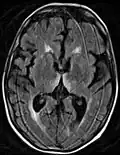

Wernicke–Korsakoff syndrome in people with chronic alcohol use particularly is associated with atrophy/infarction of specific regions of the brain, especially the mammillary bodies. Other regions include the anterior region of the thalamus (accounting for amnesic symptoms), the medial dorsal thalamus, the basal forebrain, the median and dorsal raphe nuclei,[19] and the cerebellum.[20]

Brain atrophy associated with WKS occurs in the following regions of the brain:

1. the mammillary bodies,

2. the thalamus,

3. the periaqueductal grey,

4. the walls of the 3rd ventricle,

5. the floor of the 4th ventricle,

6. the cerebellum, and

7. the frontal lobe.

In addition to the damage seen in these areas, there have been reports of damage to the cortex, although it was noted that this may be due to the direct toxic effects of alcohol as opposed to thiamine deficiency.[26]

The amnesia that is associated with this syndrome is a result of the atrophy in the structures of the diencephalon (the thalamus, hypothalamus and mammillary bodies), and is similar to amnesia that is presented as a result of other cases of damage to the medial temporal lobe.[27] It has been argued that the memory impairments can occur as a result of damage along any part of the mammillothalamic tract, which explains how WKS can develop in patients with damage exclusively to either the thalamus or the mammillary bodies.[26]

Frequently, secondary to thiamine deficiency and subsequent cytotoxic edema in Wernicke encephalopathy, patients will have marked degeneration of the mammillary bodies. Thiamine (vitamin B1) is an essential coenzyme in carbohydrate metabolism and is also a regulator of osmotic gradient. Its deficiency may cause swelling of the intracellular space and local disruption of the blood-brain barrier. Brain tissue is very sensitive to changes in electrolytes and pressure and edema can be cytotoxic. In Wernicke this occurs specifically in the mammillary bodies, medial thalami, tectal plate, and periaqueductal areas. People with the condition may also exhibit a dislike for sunlight and so may wish to stay indoors with the lights off. The mechanism of this degeneration is unknown, but it supports the current neurological theory that the mammillary bodies play a role in various "memory circuits" within the brain. An example of a memory circuit is the Papez circuit.